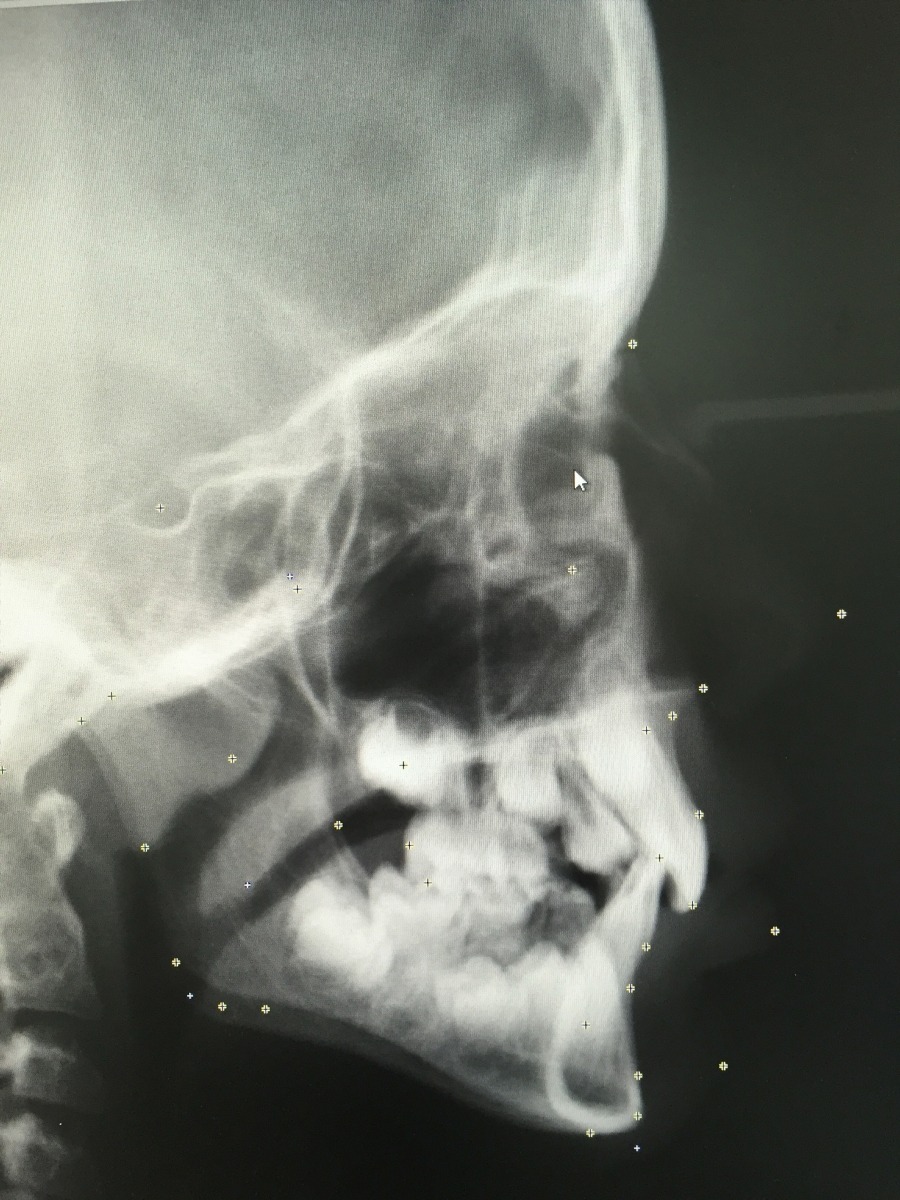

Digitale Kieferorthopädie

Die Diagnostik und Behandlungsplanung erfolgt bei uns vollständig digitalisiert. Dabei spricht man von "digitaler Kieferorthopädie". Dies ermöglicht eine präzise Diagnose, welche den Grundpfeiler für eine individuell auf den Patienten zugeschnittene Therapieplanung bildet. Wir nutzen beispielsweise eine strahlenarme digitale Röntgentechnik, mit der wir die Strahlenbelastung für unsere Patienten auf ein Minimum reduzieren und hochauflösende Bilder mit maximalem Detailgrad erhalten.